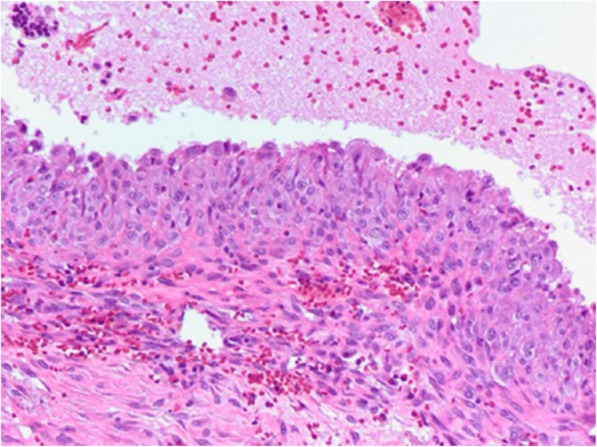

Postoperative pathology results confirmed the diagnosis of ACC and no further adjuvant treatment was applied to our patient (Fig. 3). Her postoperative course has been uneventful for 1.5 years.

Fig. 3.

Histological examination. a Anastomotic islets (blue arrows) of relatively homogeneous neoplastic cells with areas of necrosis and hemorrhagic elements (green arrows) with a geographical distribution (hematoxylin and eosin × 20). b Part of the tumor, where the neoplastic cells show nuclear pleomorphism; a few of them appear with multiple nuclei (blue arrows). Thin capillaries are evident between neoplastic cells (black arrows). Hematoxylin and eosin × 20

Further laboratory testing of post-prandial plasma cortisol and plasma testosterone levels gave normal results, mimicking a nonfunctional left ACC. Elective open adrenalectomy was scheduled without any complications and the postoperative pathology record was consistent with a pseudocyst, without evidence of malignancy (Figs. 4 and 5). She has had an uneventful course 1 year postoperatively.

Fig. 5.

Histological examination: single-stranded cyst with fibrous wall, without epithelial lining, with adherent tissue of adrenal tissue, confirming the diagnosis of adrenal pseudocyst. Hematoxylin and eosin × 20